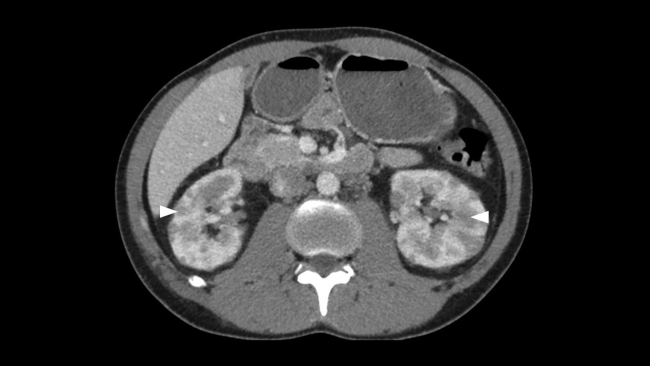

Presentamos el caso de un varón de 30 años que acudió al Servicio de Urgencias de nuestro hospital derivado por su médico de atención primaria, por la presencia de bultomas tumefactos y dolorosos a la palpación, localizados en el cuero cabelludo de un mes de evolución, predominando en zona parietal, temporal y occipital. Asociaba cefalea de características inespecíficas y astenia. Desde hacía dos semanas presentaba nódulos cervicales que impresionaban adenopatías preauriculares, retroauriculares y submandibulares. No presentaba fiebre ni sudoración nocturna. Refería pérdida de 1 a 2 kg en el último mes. Había sido tratado con minociclina 100 mg durante un mes sin mejoría. Durante su estancia, se realizó interconsulta con el Servicio de Dermatología, que completó el estudio con serologías de sífilis, virus de la inmunodeficiencia humana (VIH), hepatitis y citomegalovirus; biopsia de las lesiones de cuero cabelludo, cuyo resultado reveló linfoma / leucemia linfoblástica T; y se practicó punción aspirativa con aguja fina (PAAF) de adenopatía cervical, que confirmó el cuadro linfoide monomorfo. También se solicitó TC toracoabdominopélvica con contraste intravenoso (CIV) que puso de manifiesto: una masa mediastínica anterior que englobaba vasos con leve compresión y desplazamiento sugestiva de conglomerado adenopático y múltiples lesiones focales renales, bilaterales, así como engrosamiento apendicular sugestivos de infiltración linfomatosa (►Figs.1,2a,2b,3a,3b).

Existe una amplia variedad de manifestaciones radiológicas.1,3 La presencia de múltiples lesiones corticales nodulares es la forma más común, como en nuestro caso. Suelen ser bilaterales, de tamaño variable, típicamente de 1 a 4,5 cm de diámetro. Ante dicho hallazgo y los múltiples diagnósticos diferenciales que plantea (metástasis, carcinoma de células renales, pielonefritis, carcinoma de células transicionales, etc.) conviene completar el estudio con biopsia, si es el único hallazgo linfomatoso.2,3 En la TC sin CIV, aparecen como lesiones con una atenuación ligeramente más alta que la del parénquima circundante. La TC con CIV en fase nefrográfica es esencial porque muchas lesiones son pequeñas y afectan a la porción medular de los riñones, con mínima deformidad cortical. Los depósitos linfomatosos realzan menos que el tejido renal normal y aparecen como masas relativamente homogéneas e hipodensas.1,2